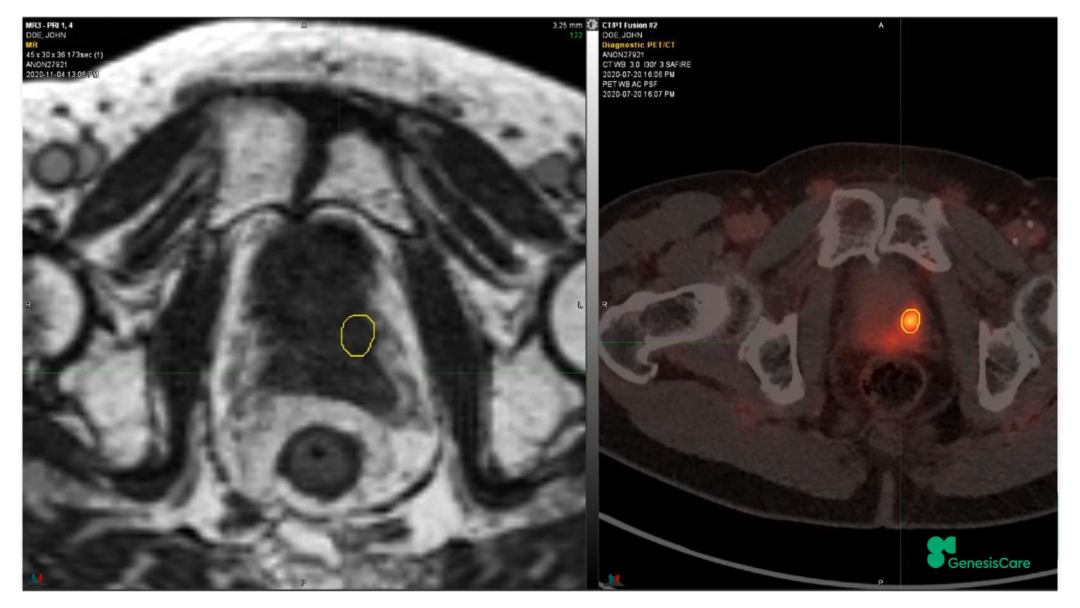

Dr. CamilleriÏÈÈÝÁËһλ72Ë꣬£¬£¬£¬£¬£¬ÔÚ2006Äê½ÓÊÜÁË55Gy/20F·ÅÁƺ󸴷¢µÄǰÏßÏÙ°©»¼Õß¡£¡£¡£¡£¡£¡£¡£ÆäʱËüµÄPSAΪ28£¬£¬£¬£¬£¬£¬¾Ö²¿ÍíÆÚ£¬£¬£¬£¬£¬£¬ÆÚ±ðΪT3aN0M0¡£¡£¡£¡£¡£¡£¡£PET-CTÏÔʾǰÏßÏÙ×óºó²¿¾Ö²¿¸ß´úл£¬£¬£¬£¬£¬£¬»î¼ìҲ֤ʵÁËÕâÒ»µã£¬£¬£¬£¬£¬£¬²¢ÇÒ»î¼ìЧ¹ûÅú×¢Ö×ÁöÇÖÈë×ó²à¾«ÄÒÏٵײ¿¡£¡£¡£¡£¡£¡£¡£½«ÆäMRIdian MRIͼÏñºÍPET-CTͼÏñÈںϺ󣬣¬£¬£¬£¬£¬ÔÙÆ¾Ö¤»î¼ìЧ¹ûÈ·¶¨°ÐÇø£¬£¬£¬£¬£¬£¬¼ûFigure 20-22£¬£¬£¬£¬£¬£¬²¢ÖÆ×÷·ÅÁÆÍýÏë¡£¡£¡£¡£¡£¡£¡£·ÅÁƼÁÁ¿Îª35Gy/5´Î£¬£¬£¬£¬£¬£¬Äý½º×è¸ôÎïºÜºÃµØ°üÀ¨ÁËÖ±³¦£¬£¬£¬£¬£¬£¬¼ûFigure 23£¬£¬£¬£¬£¬£¬°ÐÇøºÍΣ¼°Æ÷¹ÙÊÜÁ¿¼ûFigure 24¡£¡£¡£¡£¡£¡£¡£»£»£»£»£»£»£»£»¼ÕßÓÚ2020Äê12Ô½ÓÊÜÖÎÁÆ£¬£¬£¬£¬£¬£¬ËûÌåÖʺܺ㬣¬£¬£¬£¬£¬ÔÚ·ÅÁÆÊ±´úºÍÖ®ºó£¬£¬£¬£¬£¬£¬¼á³ÖÿÖÜÈý´Î5¹«ÀïÅܲ½£¬£¬£¬£¬£¬£¬Ê¼ÖÕδ·ºÆðGUºÍGI¶¾ÐÔ¡£¡£¡£¡£¡£¡£¡£ËûµÄPSA×îµÍֵΪ0.45£¬£¬£¬£¬£¬£¬ÔÚ2022Äê5ÔµÄËæ·ÃÊý¾ÝÖУ¬£¬£¬£¬£¬£¬ØºÍè¼¤ËØË®Æ½»Øµ½ÁËÕý³£µÄ33%¡£¡£¡£¡£¡£¡£¡£ÔÚ2022Äê1ÔµķÅÁƺóPSMA PETµÄͼÏñÉÏ£¬£¬£¬£¬£¬£¬Î´¼ûÖ×Áö¸ß´úл¼ûFigure 25¡£¡£¡£¡£¡£¡£¡£

Figure 23?·ÅÁƺ󸴷¢µÄǰÏßÏÙ°©»¼ÕßÔÚMRIdianÉϵķÅÁÆÍýÏë

Figure 24?·ÅÁƺ󸴷¢µÄǰÏßÏÙ°©»¼Õß·ÅÁÆÍýÏëÖаÐÇøºÍΣ¼°Æ÷¹ÙµÄÊÜÁ¿